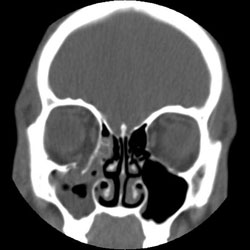

- A CT scan with fine-cut axial and coronal views, provides the best radiological assessment of orbital wall fractures (fig.3)

Fig 3: Isolated right orbital floor fracture